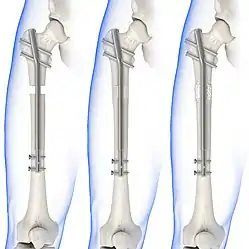

Internal fixators

Syndesmotic screws are the main, internal fixators used in surgeries for a Maisonneuve fracture. Two main types of syndesmotic screws are used: trans-syndesmotic screws (positioned at the level of the syndesmosis) and supra-syndesmotic screws (positioned above the syndesmosis).[14]

Based on several clinical results, syndesmotic screws are recommended to be fixed at least 1 centimetre proximal to the tibiofibular syndesmosis or 4 to 6 centimetres proximal to the tibiotalar joint line.[4][15] Cadaveric analyses, from a comparative study published in Foot & Ankle International in 1997, suggest that screw fixation at 2 centimetres proximal to the tibiotalar joint line is also adequate.[16] Biodegradable implants such as bioabsorbable screws, which do not require postoperative removal, may be used as an alternative to metallic hardware. However, biodegradable implants still limit rotation of the ankle and dorsiflexion of the foot.[4][6][13]